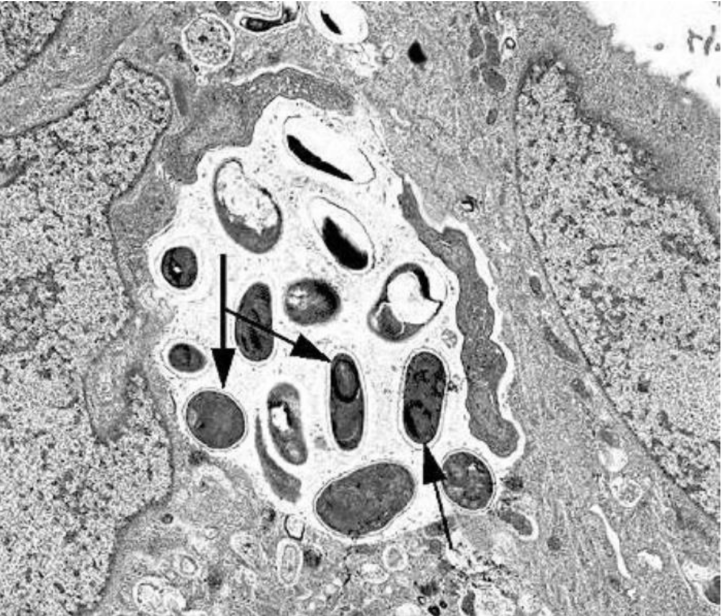

图1 肠脑炎微孢子虫形态结构[2]

- 孢子:椭圆形,大小为(2.0-2.5) μm×(1.0-1.5) μm,缠绕5-7圈排列成1行,厚的孢子体外膜发育成为孢子的外壁,在小肠上皮细胞胞浆内的纳虫空泡(parasitophorous vacuoles)内生长发育和繁殖。

- 裂殖体:圆形或椭圆形,大小约为7 μm×6 μm,电镜下可见其电子致密度低于宿主的胞浆,常含有电子疏松包含体(electron-lucent inclusions)。

- 孢子母体:椭圆形,大小约为8 μm×7 μm,电子致密度大于裂殖体。在孢子体分裂发育成孢子母细胞前形成极管和锚定盘的电子致密前体。